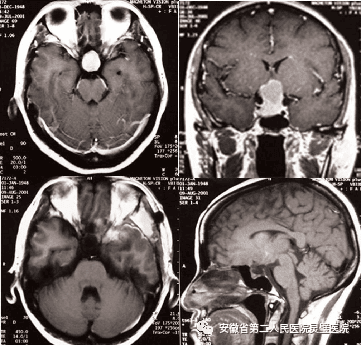

颅脑创伤是神经外科常见病、多发病,近十年来,我们成功诊治了大量重型颅脑损伤患者,尤其在特重型颅脑损伤、原发性脑干伤、弥漫性轴索损伤等方面积累了丰富的经验,并形成了以“神经多模态监测、亚低温治疗、镇静镇痛、大骨瓣减压以及精准化脑保护”等核心技术为特色的一体化标准化救治方案,重型颅脑创伤患者死亡率逐年降低,达到国内一流水平。

硬膜下血肿、脑挫裂伤术前和术后 颅内压监测